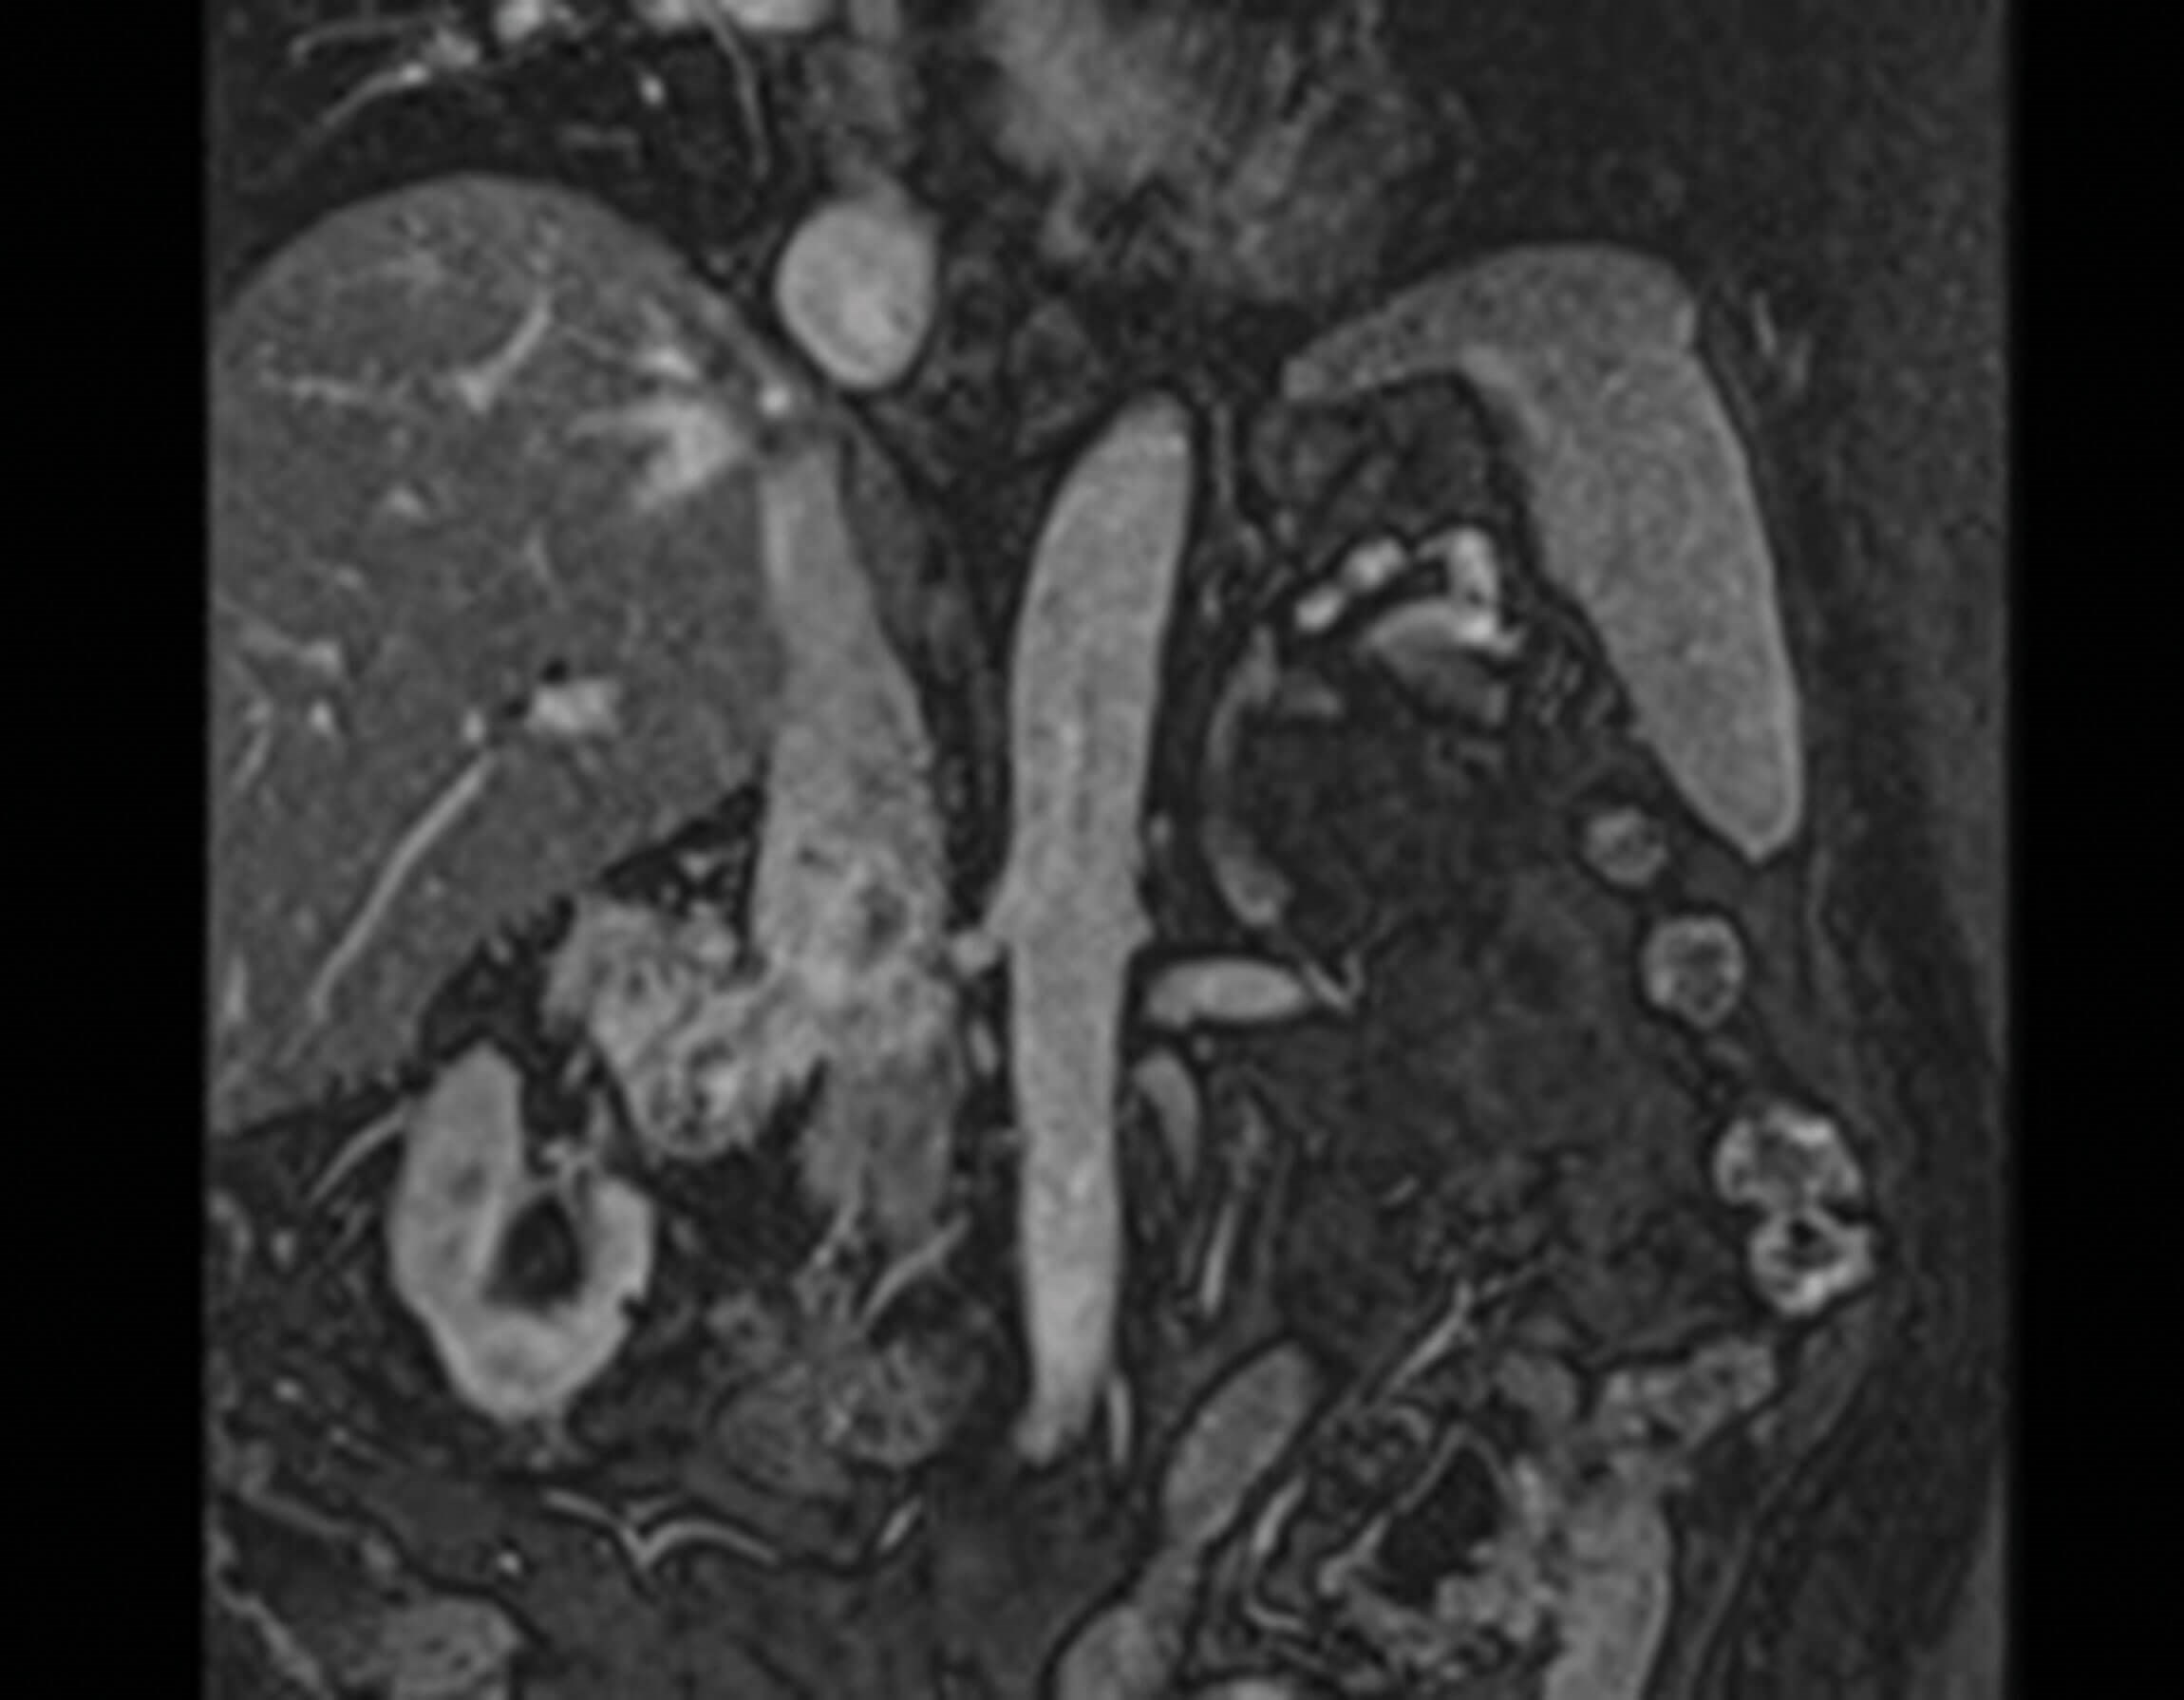

Figure 2.

1. This is an axial and coronal section of an MRI, which demonstrates a large right renal tumour. The tumour extends into the inferior vena cava but remains below the diaphragm. This patient therefore has T3bN0Mx disease. RCC staging follows the TNM staging outlined in article 1 ‘Localised Renal Cancer’.